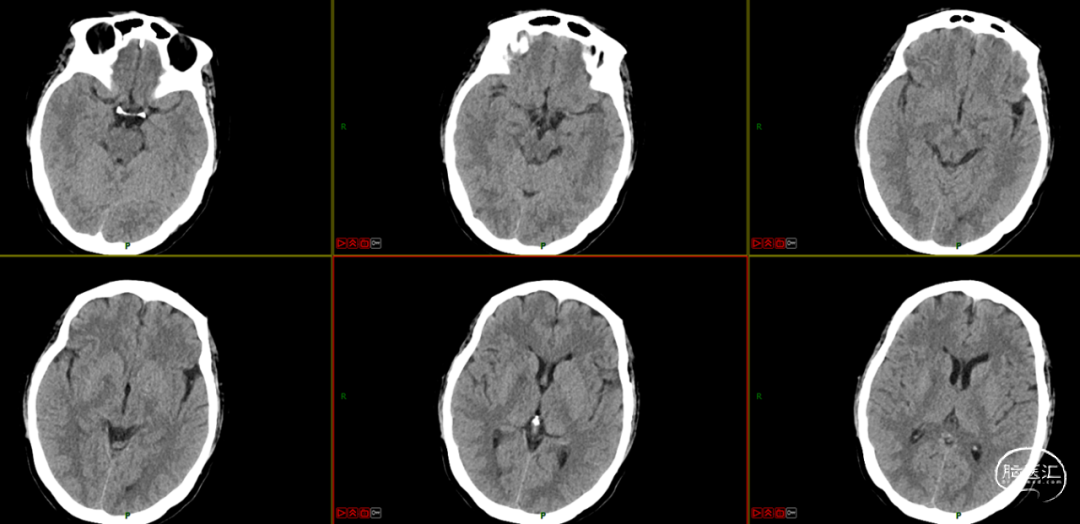

术后处理及复查

术后第一天颅脑CT

术后第三天转入普通病房。查体:神志清楚,对答切题,双侧瞳孔等大等圆,D=3.0mm,双侧瞳孔对光反射灵敏,伸舌居中,四肢肌力肌张力正常,双侧巴氏征未引出。NIHSS评分2分,mRS评分1分。

术后第七天,患者病情明显好转,无特殊不适,予以办理出院。

出院时查体:神志清楚,对答切题,双侧瞳孔等大等圆,D=3.0mm,双侧瞳孔对光反射灵敏,伸舌居中,四肢肌力肌张力正常,双侧巴氏征未引出。NIHSS 0分,mRS 0分。